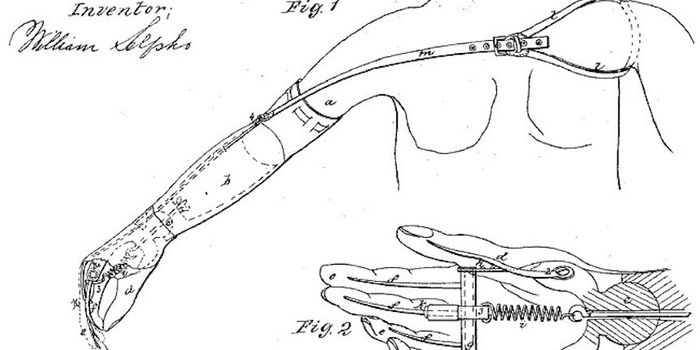

APR 15, 2016Clinical & Molecular DXImagine pouring a cup of coffee, stirring it, and lifting the cup to drink. Sounds simple for most people, but being abl ...